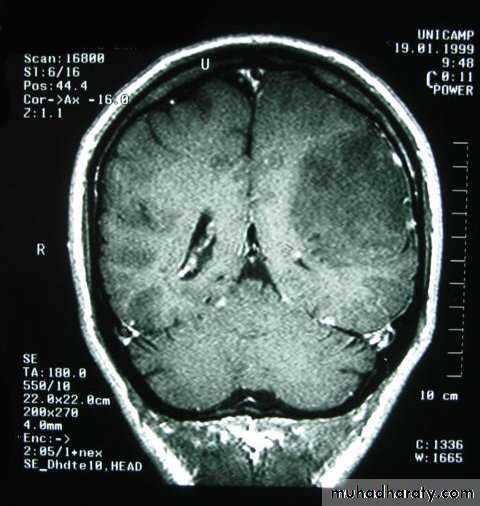

Metastatic Brain Tumours

Metastatic Brain Tumours Pre contrast CT

Metastatic Brain Tumours Post contrast CT